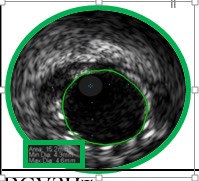

1680. На изображении представлено исследование коронарных артерий